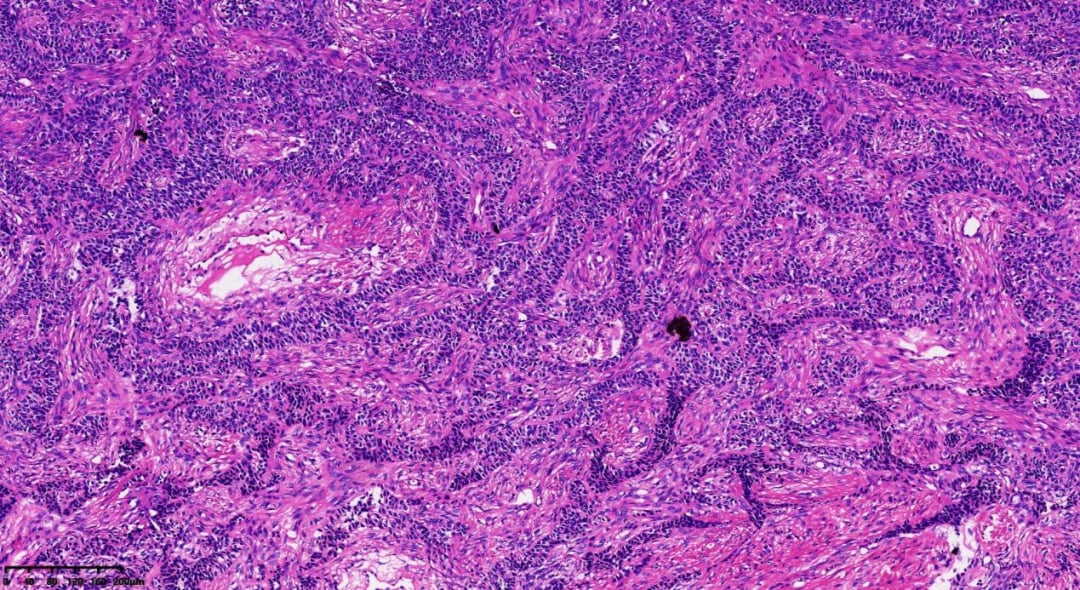

肿瘤呈梁状、条索状分布

肿瘤弥漫性分布,肿瘤细胞胞质相对较少,呈单一表现

- 组织病理学:瘤组织排列模式多样,同一肿瘤内可能出现多种结构,包括弥漫性、结节状、小梁状、条索样、岛屿状、滤泡状、波浪状、脑回样及肉瘤样。少数病例可见囊性变区域,甚至形成假乳头。瘤细胞通常胞质稀少、淡染,大小相对一致,界线不清,呈卵圆形或多边形,细胞核轮廓不规则,可见核沟或呈咖啡豆状。核分裂象通常较少见,75%的病例中每10个高倍视野(HPF)少于3个。